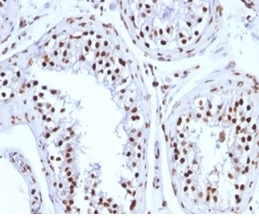

Immunohistochemistry (IHC)

1-2ug/ml

30 min at RT. Staining of formalin-fixed tissues requires heating tissue sections in 10mM Tris with 1mM EDTA, pH 9.0, for 45 min at 95°C followed by cooling at RT for 20 minutes

A-431, HeLa, LNCap or Jurkat cells. Human heart tissue lysate. Breast carcinoma.